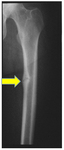

Radiograph of the femoral shaft in a patient with osteomalacia demonstrating a "pseudofracture" (also known as Looser's zone) on the medial aspect of the mid-femoral shaft

From the collection of Bridget Sinnott, MD